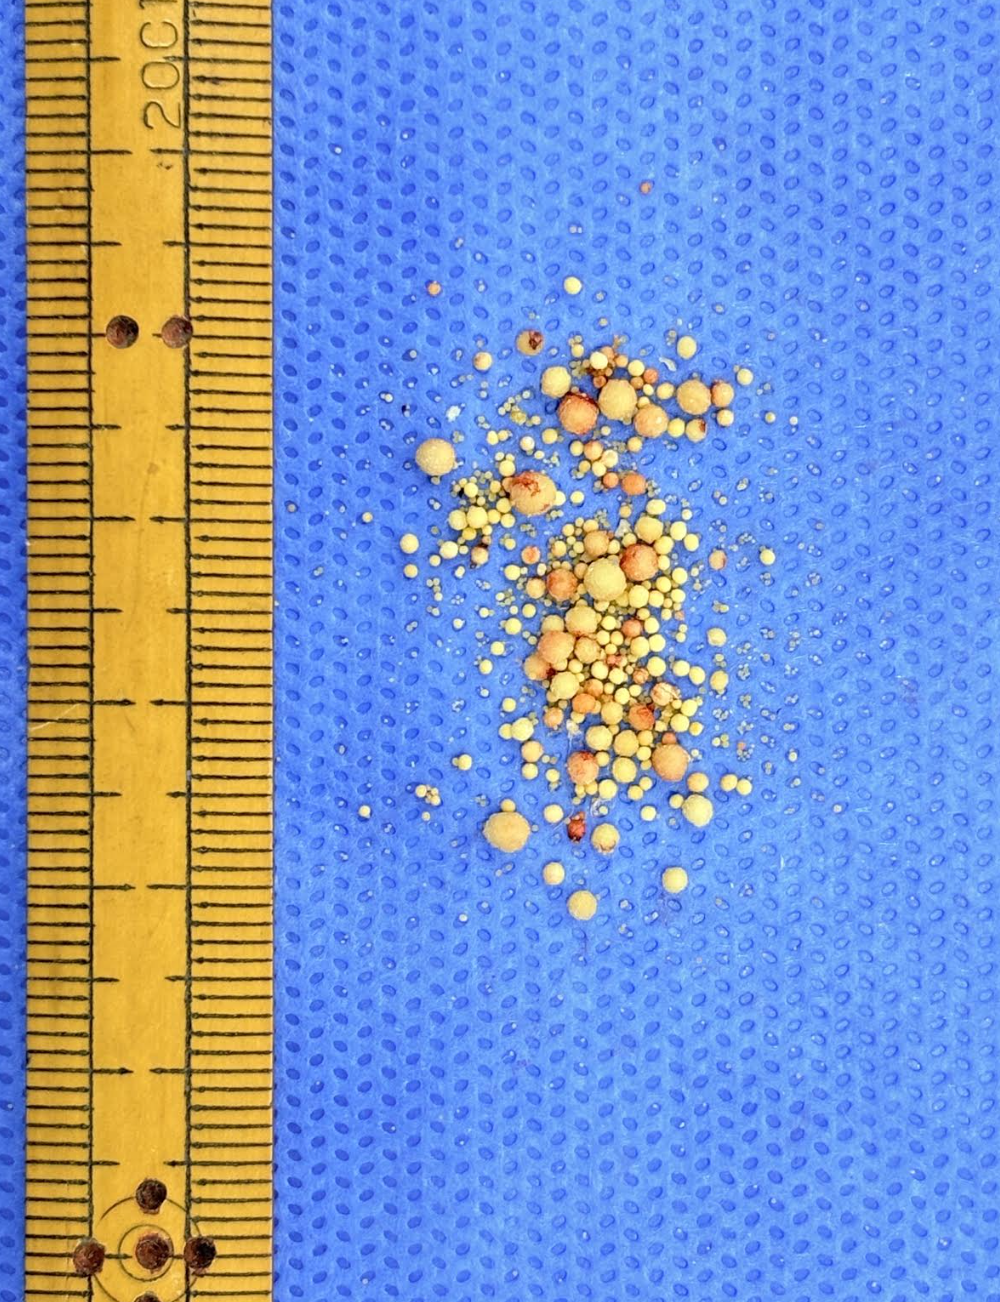

↑手術で取り除いた膀胱結石

結石が大きい場合や尿道を塞いでいる場合は、膀胱切開手術で取り除く